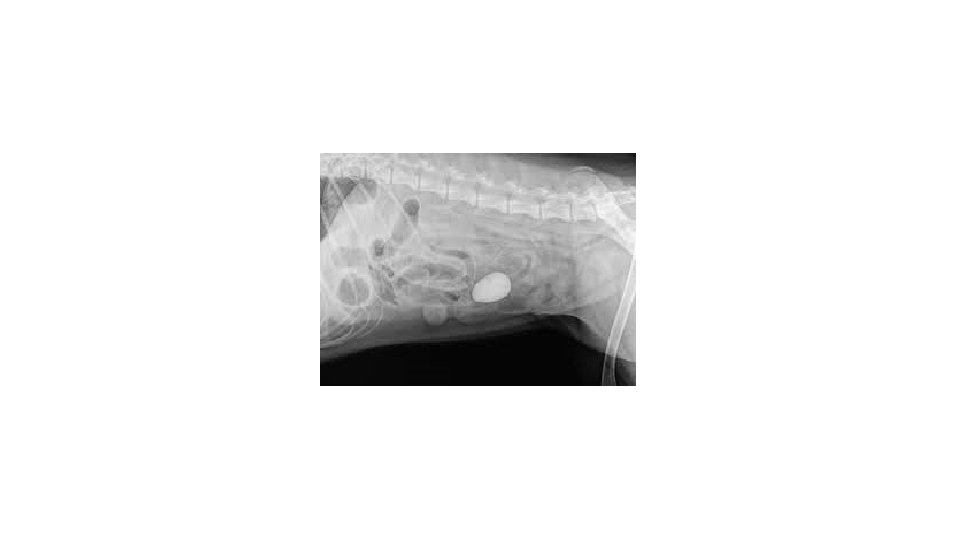

• Site of location of obstruction ØHigh obstruction ØLow obstruction • AETIOLOGY • Mechanical obstruction Ø(i) Intraluminal mass • Heavy nodular worm infestation in calves.

The intestinal obstruction (hair pellets) in rabbit

Distended small bowel obstructed by bundles of Ascaris lumbricoides worms